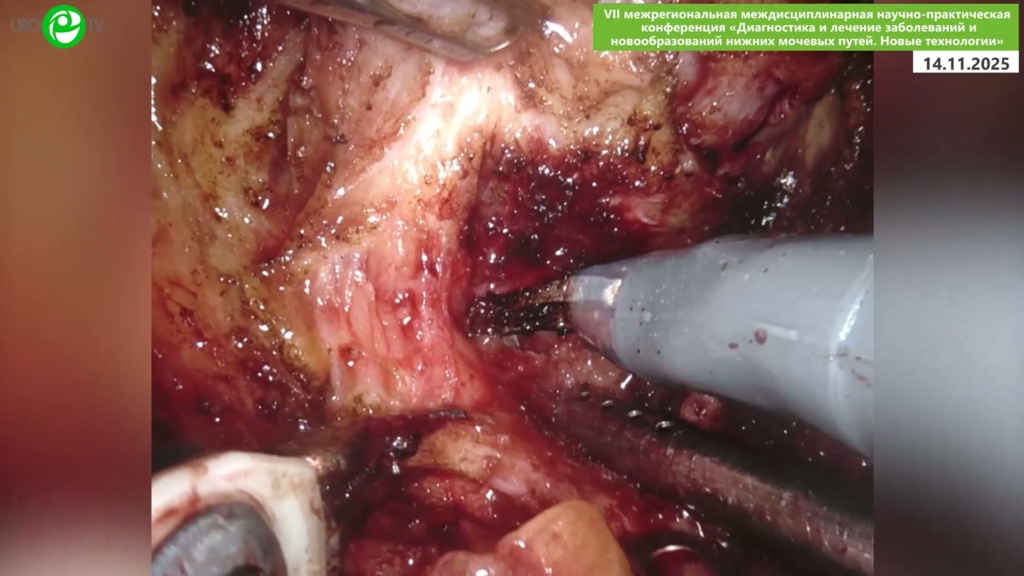

Безруков Е.А. - Робот-ассистированная простатэктомия с нервосбережением